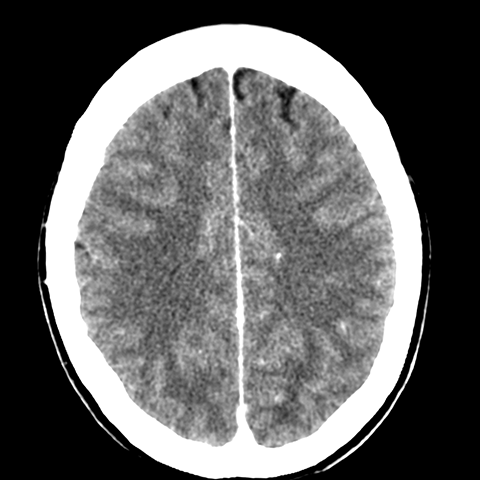

Cerebral Hemispheres, CT (normal) [1 of 6]